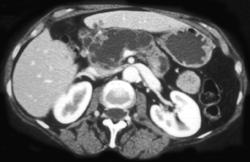

Pancreatic Adenocarcinoma With Implants